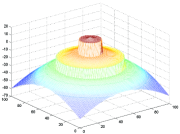

In the continuous domain of energy, a function may be classified as non-convex, convex, pseudoconvex or quasiconvex (Figure 4). Below, we define each of these terms mathematically.

Pseudoconvex functions share the property of convex functions in that, if , then is a global minimum of . The pseudoconvexity is strictly weaker than convexity. In fact, every convex function is pseudoconvex. For example, is pseudoconvex and non-convex. Also, every pseudoconvex function is quasiconvex, but the relationship is not commutative, e.g. is quasiconvex and not pseudoconvex.

In this paper we focus on convex and non-convex optimization problems; more details on quasiconvex problems can be found in (dos Santos Gromicho, 1998). In the continuous domain, an optimization problem must meet two conditions to be a convex optimization problem: 1) the objective function must be convex, and 2) the feasible set must also be convex. The drawbacks associated with non-convex problems are that, in general, there is no guarantee in finding the global solution and results strongly depend on the initial guess/initialization. In contrast, for a convex problem, a local minimizer is actually a global minimizer and results are independent of the initialization. However, non-convex energy functional often give more accurate models (see Section 3.5).

An ideal method improves both optimizibility and fidelity without sacrificing either property (green contour in Figure 5).